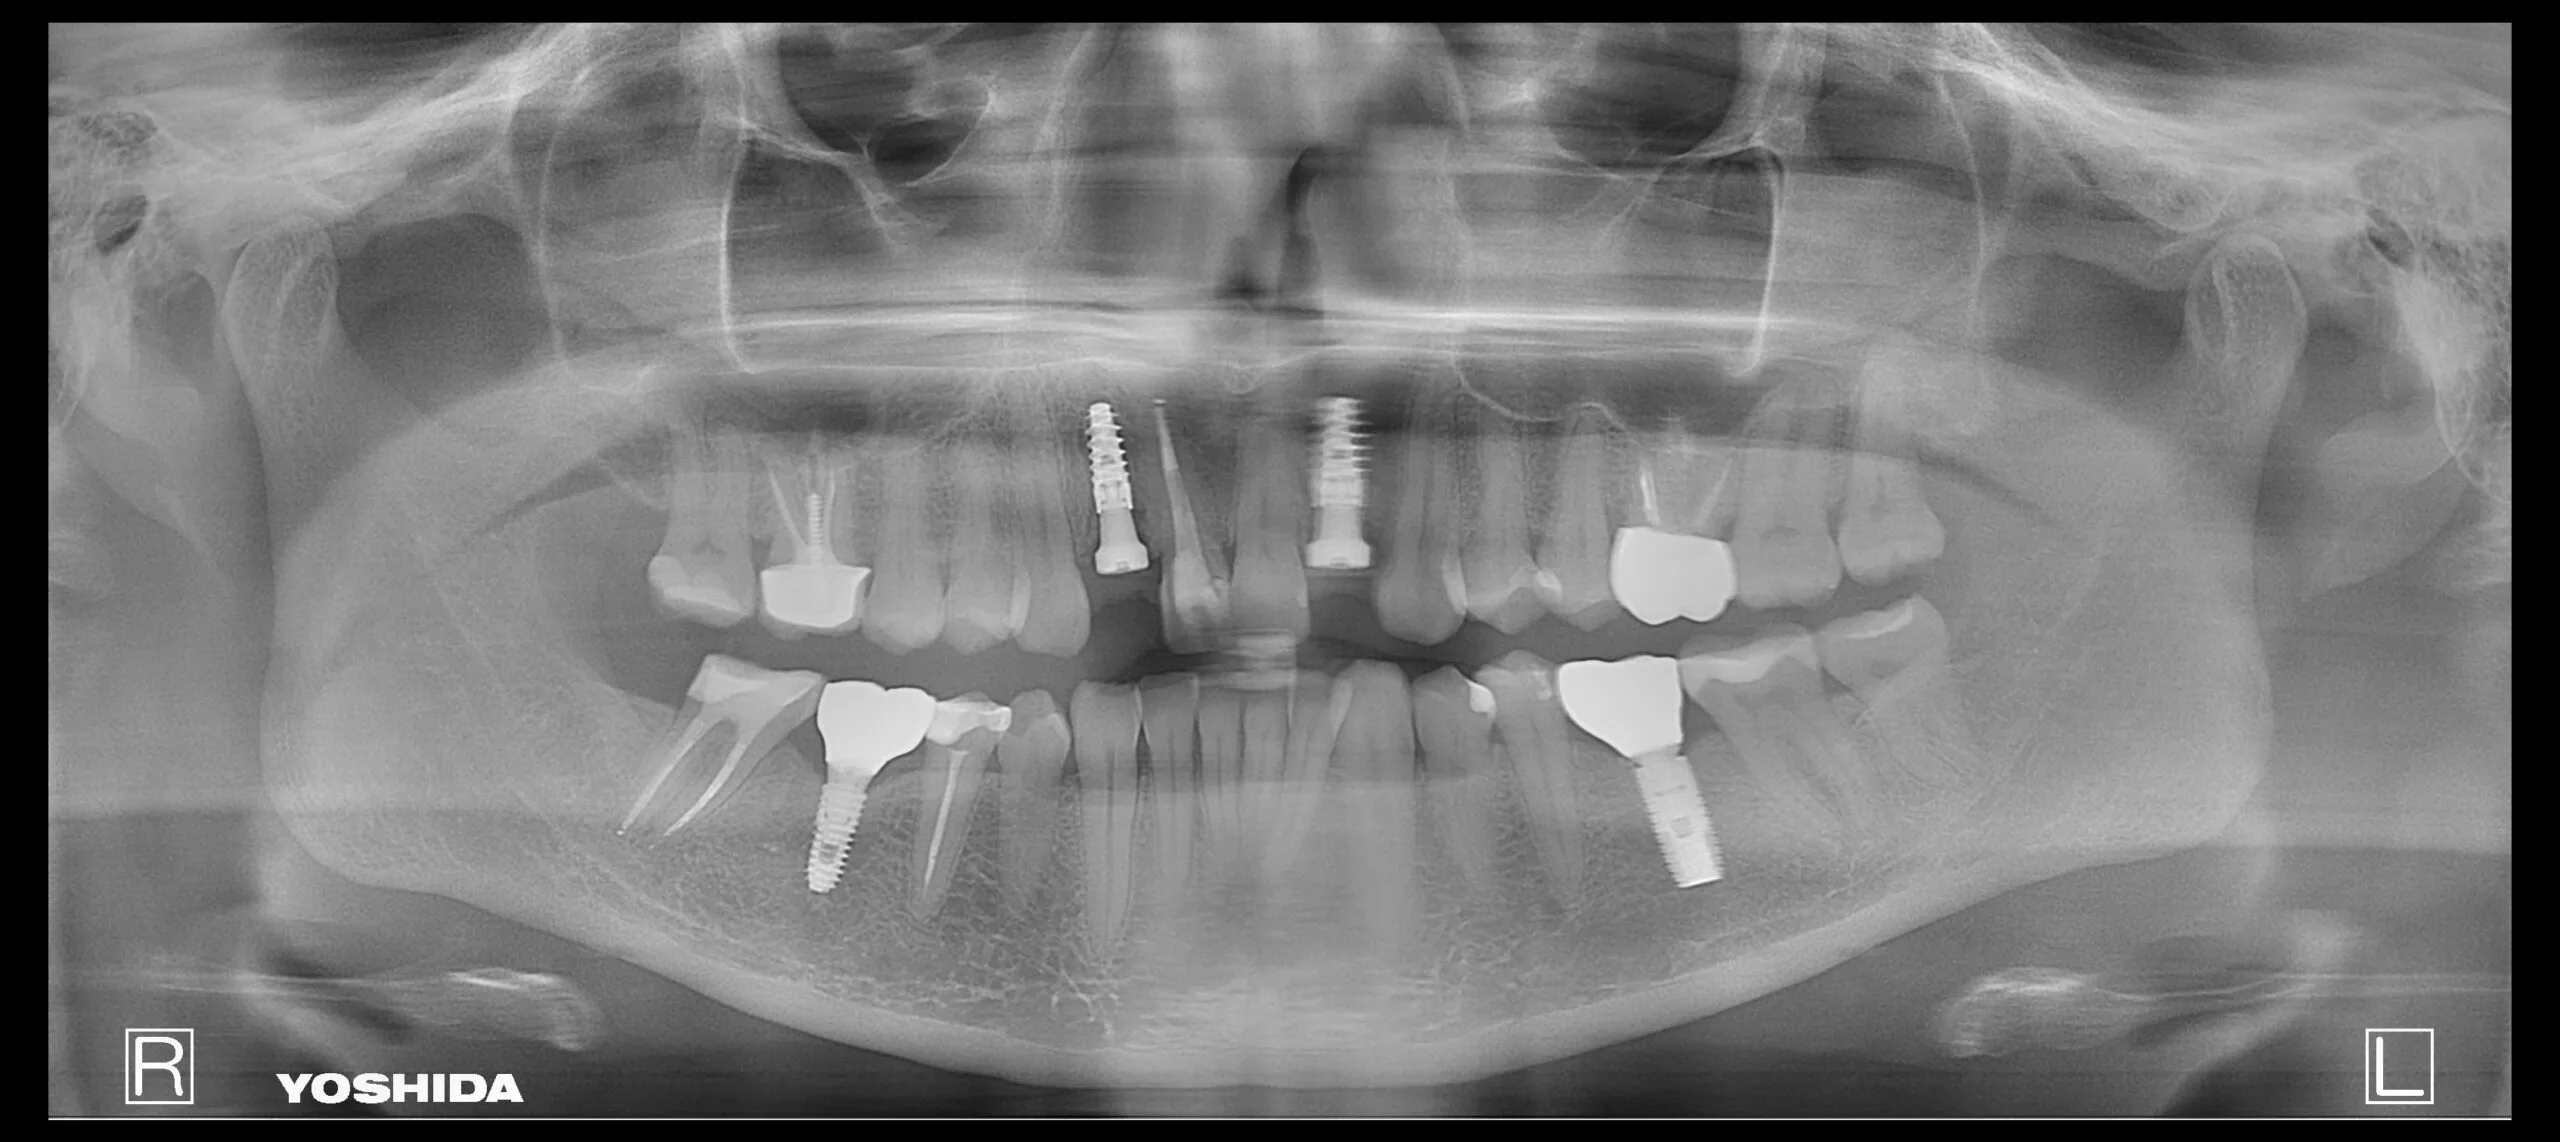

Pacientė kreipėsi dėl skilusių 12 ir 22 dantų šaknų, todėl jautė skausmą ir reikėjo skilusius dantis pašalinti. Pašalinus, buvo įsriegti implantai, jiems prigijus, suformuotos gijimo galvutės ir pritaikyti laikini vainikėliai ant implantų, kad pacientė priprastų prie naujų dantų formos ir pritaikytos spalvos. Net laikinų restauracijų sunku atskirti nuo natūralių dantų ir galime pilnavertiškai džiaugtis savo dantų būkle.